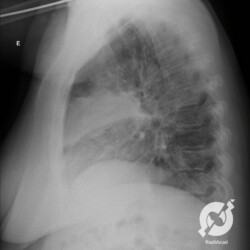

E o nome dado a esta alteração radiográfica que corresponde à substituição do ar alveolar por líquido é a consolidação alveolar.

Uma consolidação alveolar é, por definição, uma opacidade (imagem densa, branquinha) homogênea ou às vezes heterogênea (pela presença de calcificações ou cavidades), de limites mal definidos, exceto quando toca a pleura da parede ou das cissuras pulmonares. É um termo usado tanto em radiografia, como em tomografia computadorizada. Na tomografia, um outro termo é usado: vidro fosco, que é uma opacidade (branquinha mas não tanto como a consolidação), que borra o pulmão mas deixa ver os vasos de permeio (igual bigode de adolescente: dá pra ver todo o fundo).

Nós vamos mostrar aqui um pequeno apanhado de pneumonias de variados agentes, em diversos segmentos e lobos pulmonares, com extensões variadas. O objetivo é identificar o padrão radiológico de consolidação alveolar e não determinar o agente infeccioso, isso vai ser assunto para mais adiante. Aliás já antecipo que é fundamental saber localizar a lesão, porque alguns destes bichos gostam de determinados segmentos, alguns tumores também têm as suas preferências, então localização é fundamental. Se localização não fosse importante, um apartamento na beira do mar sairia o mesmo preço de um apartamento de frente pra BR-101, concordam?

Seguem alguns dos nossos casos de pneumonia para vocês treinarem os olhos e não se apavorarem nos plantões.